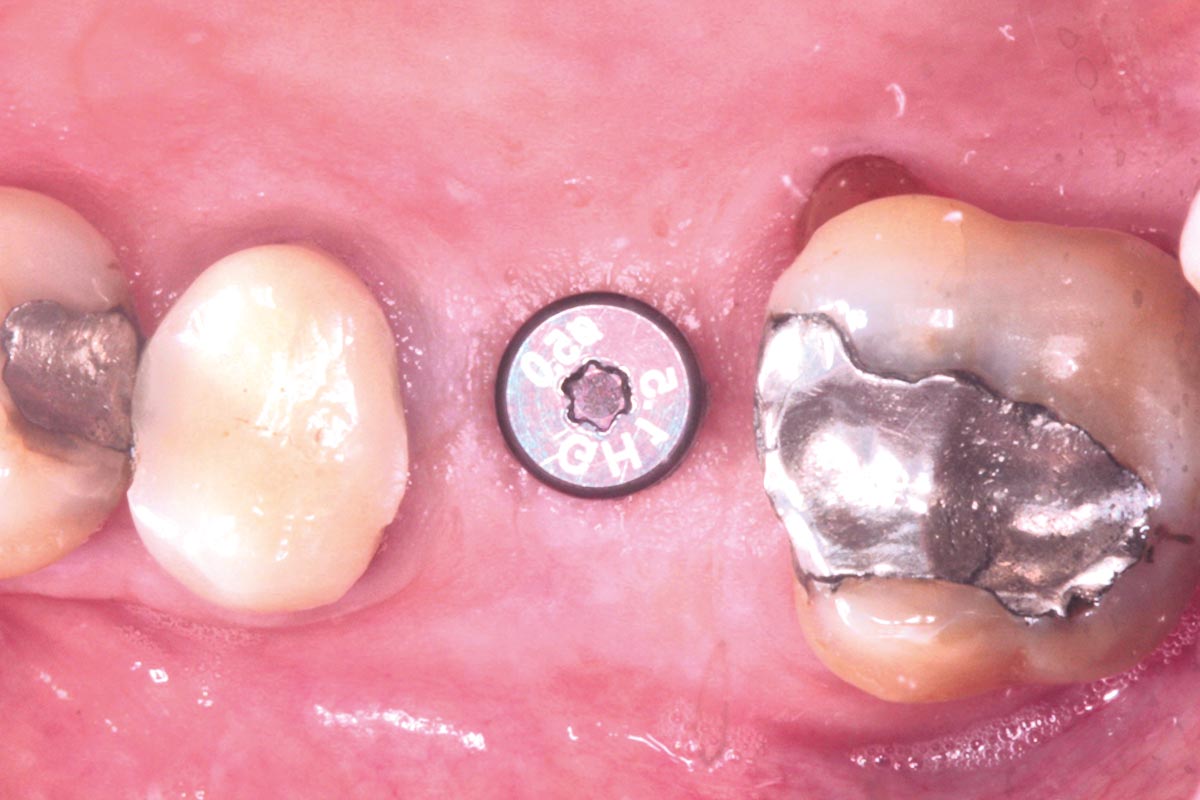

28/35 - Application of the healing cap after the second stageMaxillary sinus cyst removal using the Crocodile Technique and subsequent lateral sinus lift - Dres. C. Scognamiglio and A. Perucchi